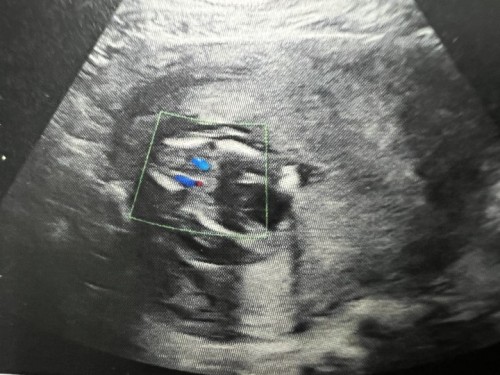

แม่ๆช่วยดูรูปอัลตราซาวด์ให้หน่อยค่ะว่าชาย/หญิง

รูปอัลตราซาวด์ตอน18+3weekค่ะ

เห็นไม่ชัดเลยค่ะแม่ ถ้าอยากชัวร์ๆ ต้องรอสัปดาห์ครรภ์มากกว่านี้นิดนึงน๊า